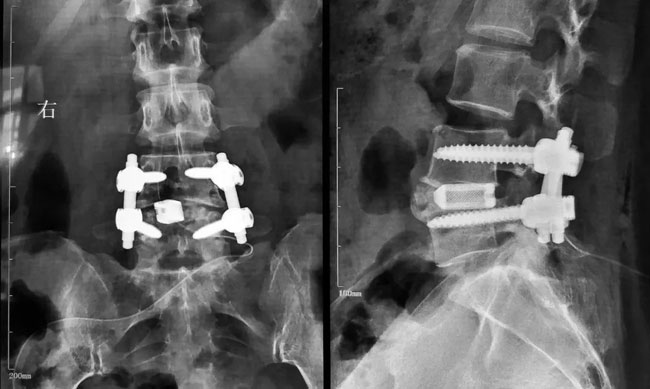

高放射線可見(jiàn)性可實(shí)現(xiàn)更好的輪廓顯示,便于術(shù)中、術(shù)后清晰地觀察融合器,評(píng)估椎體終板與植入物的接觸情況,以及骨融合情況。

X射線清晰可見(jiàn)植入物,CT掃描無(wú)散射,MRI偽影減少,無(wú)鉭標(biāo)記物散射。